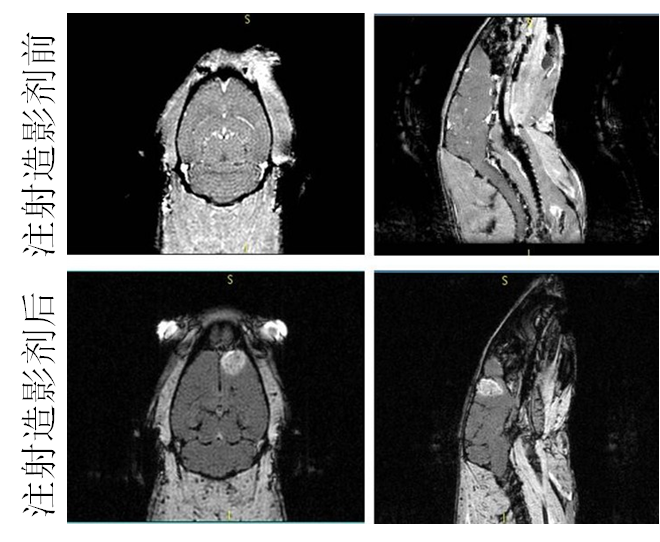

´ÅÐÔÄÉÃ×Á£×ÓÓÃ×÷´Å¹²Õñ³ÉÏñ£¨MRI£©ÔìÓ°¼Á

ÒÔǰֻÊÇÔÚÓ¡ÏóÖУ¬ÎªÁËÕâÊÂÕÒÁËһϣ¬»¹Ã»ÓÐÀ´µÃ¼°ÈÏÕæ¶Á¡£Ï£ÍûÓÐÖú http://www.ema.europa.eu/docs/en ... /01/WC500067464.pdf from wiki: http://en.wikipedia.org/wiki/MRI_contrast_agent Iron oxide: Superparamagnetic[edit] Two types of iron oxide contrast agents exist: superparamagnetic iron oxide (SPIO) and ultrasmall superparamagnetic iron oxide (USPIO). These contrast agents consist of suspended colloids of iron oxide nanoparticles and when injected during imaging reduce the T2 signals of absorbing tissues. SPIO and USPIO contrast agents have been used successfully in some instances for liver tumor enhancement.[17] Although SPIOs and USPIOs have been approved for use in the past, it appears that all of the agents listed below are no longer available with the exception of the oral iron oxide contrast agent, Lumirem/Gastromark. Feridex I.V. (also known as Endorem and ferumoxides). This product was discontinued by AMAG Pharma in November 2008.[18] Resovist (also known as Cliavist). This was approved for the European market in 2001, but production was abandoned in 2009.[19] Sinerem (also known as Combidex). Guerbet withdrew the marketing authorization application for this product in 2007.[20] Lumirem (also known as Gastromark). Gastromark was approved by the FDA in 1996.[21] Clariscan™ (also known as PEG-fero, Feruglose, and NC100150). Development was discontinued due to safety concerns.[22] |